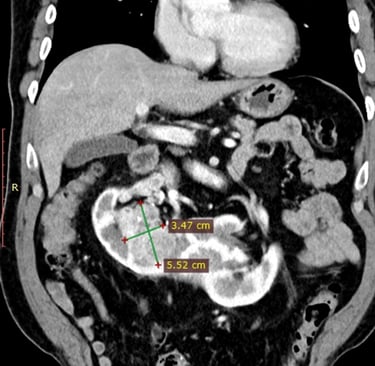

Ліва та права нирки були з’єднані перешийком висотою майже 5 см, що формувало характерну форму підкови (див. КТ-знімок).

пухлину нижнього сегмента правої половини підковоподібної нирки

пухлинний тромб у правій нирковій вені